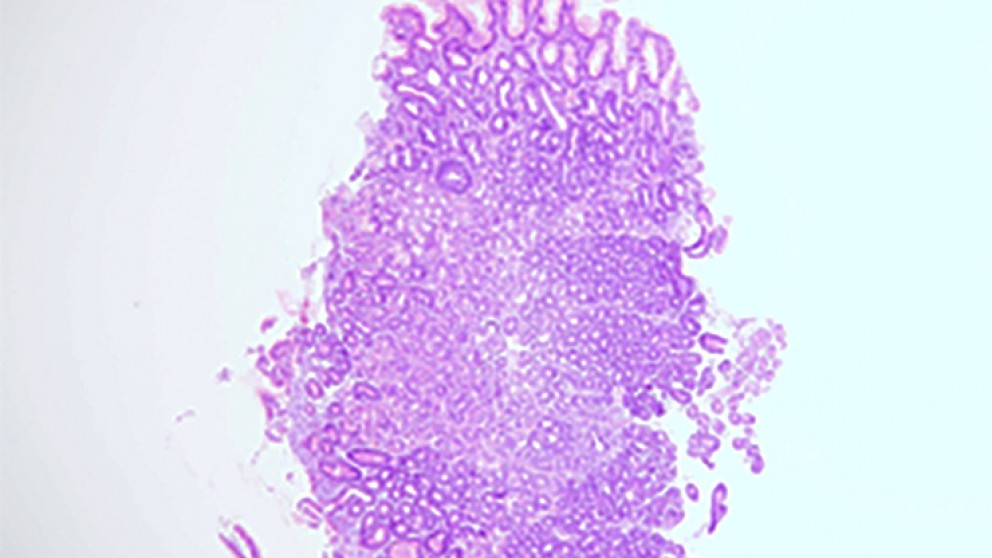

Chronic gastritis is a common condition that occurs when an inflammatory infiltrate is present in the gastric mucosa. Diverse factors can cause such inflammation to develop, including food, common bacteria (particularly Helicobacter pylori) and even some viruses. Although the inflammatory infiltrate itself may not cause a disease per se, in some cases gastritis will evolve into atrophic gastritis, ulcers or gastric cancer. Clinicians therefore need to be aware of when gastritis is a harmless condition that can be left alone and when further action is required. In addition, many patients and some clinicians use the term ‘chronic gastritis’ to describe symptoms, mostly those of dyspepsia. This misuse of the terminology can lead to the erroneous conclusion that a diagnosis is being discussed and not a symptom. Here we address these mistakes and some of the others that are frequently made when managing patients with chronic gastritis. We discuss how to avoid making the mistakes to ensure that patients are managed adequately while reducing over treatment.

Mistakes in the management of chronic gastritis and how to avoid them